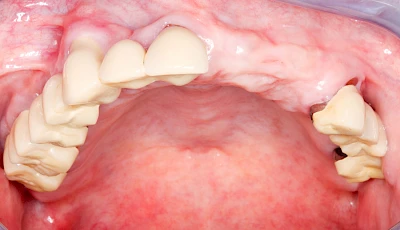

Heute werden in Deutschland Menschen mit Lippen-Kiefer-Gaumenspalten bereits ab Geburt von Experten verschiedener Fachrichtungen (Mund-Kiefer-Gesichtschirurgen, Kieferorthopäden, Logopäden) betreut, damit entsprechende Korrekturen schon frühzeitig erfolgen können. Gerade jedoch bei älteren Menschen ist dies nicht immer geschehen. Diese Menschen tragen häufig technisch aufwendige Zahnprothesen.